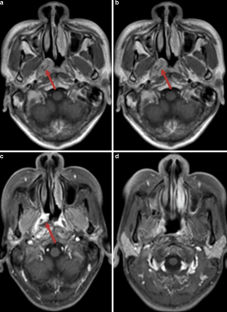

A 39-year-old man presented with a several-week history of nasal obstruction and epistaxis. Computed tomography (CT) and magnetic resonance imaging (MRI) revealed the presence of a retro-odontoid nonenhancing soft tissue mass.

The endoscopic biopsy demonstrated that the mass was amyloid in nature. An extensive systemic workup revealed an absence of inflammatory process, systemic amyloidosis, or plasma cell dyscrasia. The patient was treated with a combination of surgery and radiotherapy, showing no evidence of recurrence or progression at his 1‑year follow-up.